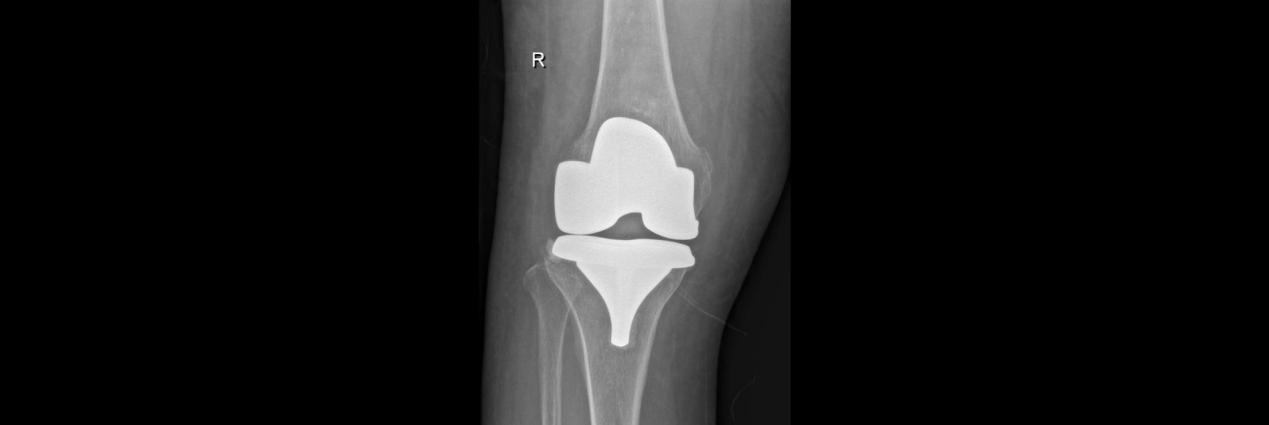

术前

66岁的孙女士,因右膝疼痛3年,加重2年于2月17日入院,患者曾接受关节腔玻璃酸钠等保守治疗,短期效果可,近期效果不明显,膝关节疼痛严重,每走一步都扎心的疼。入院后,董孟政副主任、黄贵云副主任一齐查看患者情况,经拍片检查诊断为膝关节骨性关节炎严重,定于2月19日为患者行关节置换术。

术后

术中,见患者膝关节软骨磨损严重,更换全膝关节假体。术后指导功能锻炼,术后第1天患者便可下地活动,术后3天已无需助行器自行活动,膝关节疼痛明显减轻,患者对手术效果非常满意,现已顺利出院。